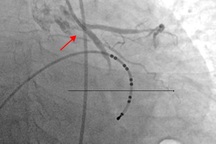

Sau 8 ngày chạy ECMO, tim bệnh nhân phục hồi, chức năng co bóp cơ tim tốt và được cai ECMO thành công. Chẩn đoán bệnh thời điểm này là sốc tim, suy tim cấp, viêm cơ tim tối cấp, viêm phổi nặng, nhiễm trùng huyết. Hiện tại, bệnh nhân tỉnh, tiếp xúc tốt, thở được khí trời, huyết áp bình thường, ăn uống được và đã cai máy thở. Dự kiến, bệnh nhân sẽ được xuất viện vào đầu tuần sau.

Phó giáo sư Phạm Văn Quang, Trưởng khoa Hồi sức tích cực - Chống độc (ICU), Bệnh viện Nhi đồng 1 cho biết, quá trình điều trị, bệnh nhi ngưng tim đến 60 phút, phải vừa cấp cứu ngưng tim, vừa đặt ECMO. Đến nay, có thể khẳng định bệnh nhi được cứu sống ngoạn mục, không để lại di chứng.

Bệnh nhi được chạy ECMO trong 8 ngày (Ảnh: BV).